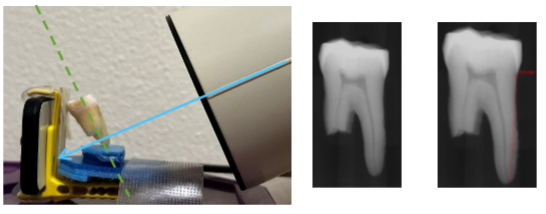

This projection technique is preferred, produces images with less distortion, anatomy may prevent strict adherence

Position receptor parallel to long axis of teeth and direct central xray perpendicular to both

Paralleling Technique

In the paralleling technique, where is the receptor placed for maxillary imaging?

Toward the center/height of the palatal vault

In the paralleling technique, where is the receptor placed for mandibular imaging?

Deep in the lingual vestibule, pushing tongue out of the way toward midline

Long cone is used to ____ the source-object distance

Increase